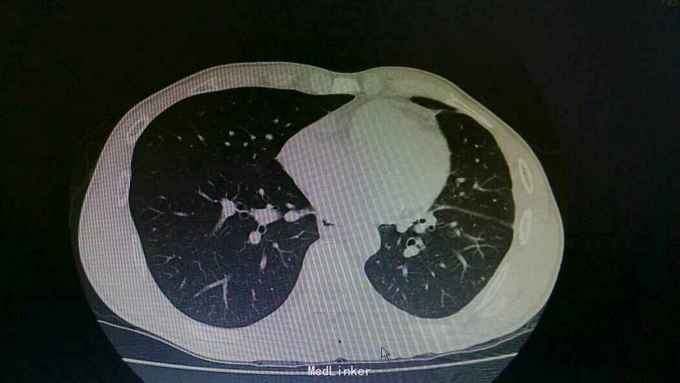

诊断:结核性胸膜炎 治疗:入院予以左侧胸水引流,T-SPORT A68,B24。予以四联抗结核治疗。辅查胸部CT患者左侧胸水减少,病情好转。